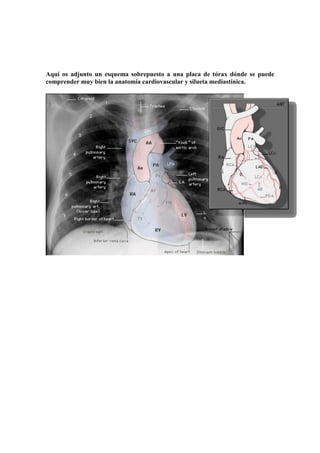

En la proyección PA de torax podemos identificar los contornos del mediastino que

corresponden a diferentes estructuras. Debemos conocerlas y son:

c

b

d

e

f

a

a. borde derecho del corazón

b. vena cava superior

c. pared derecha de la tráquea

d. botón aórtico

e. aorta descendente

f. borde izquierdo del corazón

Aquí os adjunto un esquema sobrepuesto a una placa de tórax dónde se puede

comprender muy bien la anatomía cardiovascular y silueta mediastínica.